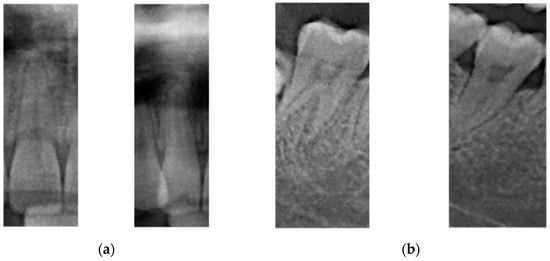

At a large scale, the overall arrangement and brightness of dental X-ray images from different patients vary significantly. The difference at the micro level is manifested in local characteristics. The reason for this may be because of subtle variations in the shape of the teeth of different patients. For example, the central teeth shown on the left of Figure 4a are larger than the ones at the right; i.e., the edges and corners are more obvious, the overall teeth are straighter, and the imaging effect is also different, which is reflected in the brightness and sharpness. The tooth difference in Figure 4b is more evident. Similarly, image transformation methods based on manual processing (through, for example, rotation, translation, elastic deformation, and mirroring) can simulate new samples that are different from the original image; thus, using these methods can increase the effectiveness of the model.

Microscopic characteristics of the same category of teeth. (a) The Central incisor tooth from different person, (b) The Second molar tooth from different person.